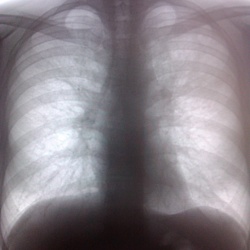

Молодой человек 1986 г.р. проходит медосмотр, жалоб нет. Что это может быть?

Первый снимок это рентген грудной клетки на передвижном рентгенаппарате Армане.

Вторая серия снимков: флюоро...